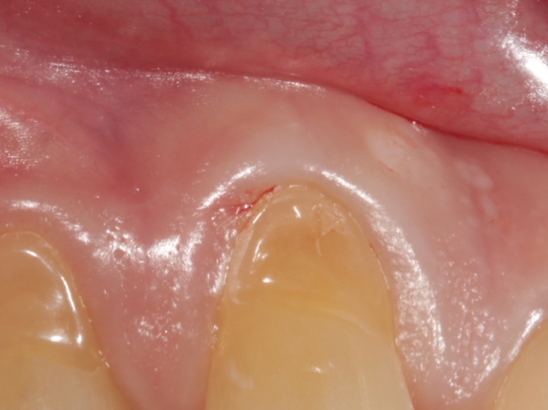

3. 근첨성 치주염

신경을 잃은 치아에 발생하기 쉬운 문제입니다. 치아 뿌리 끝에 고름이 차는데 이 염증이 턱뼈 쪽을 향해 서서히 내려가면서 잇몸을 뚫고 나오면서 고름이 나게 되는데 고름이 나오지 않는 경우도 있습니다.

이 잇몸 염증으로 고름이 나오게 되면 턱뼈 내 압이 감소하면서 위화감 정도만 느껴지는 경우가 많습니다. 하지만 고름이 나지 않으면 고름이 나오는 출구가 없기 때문에 압력이 세어져 갑자기 아주 심함 통증을 느끼게 될 가능성이 높습니다.